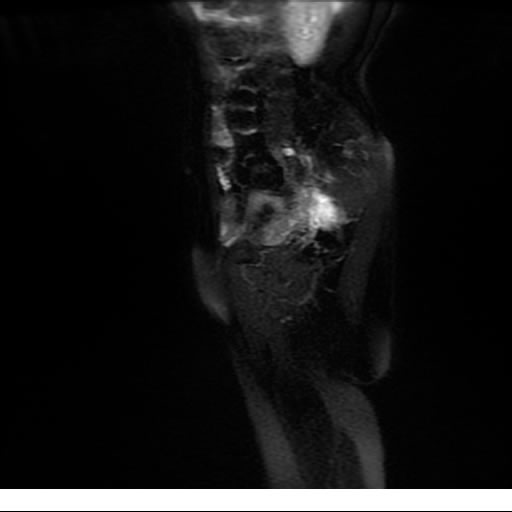

Se realizan adquisiciones en diferentes planos, con secuencias Spin echo y GRE, ponderadas a T1 y a T2, se utilizan pulsos de saturación de grasa y se administra medio de contraste a base de gadolinio.

El útero está en retroversión, retroflexión, y en posición central, se observa liquido en la cavidad endometrial, debido a la presencia de un Ca endometrial; en el anexo derecho se observa una masa quística que mide 3.8 x 2.2 cm de diámetro, corresponde a un quiste bilobulado, posee pared gruesa con componente solido puede tratarse de un Cistoadenocarcinoma, el cual realza con el medio de contraste de forma importante, entra dentro de una clasificación O-Rad tipo IV compatible con un Cistoadenocarcinoma

O-RAD tipo IV, Cistoadenocarcinoma